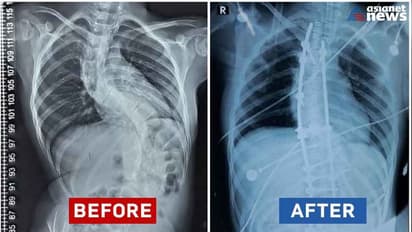

ഇത് സാധാരണ കുട്ടികളില് കാണുന്ന adolescent idiopathic scoliosisന്റെ ചികിത്സയേക്കാള് ബുദ്ധിമുട്ടുള്ളതും സങ്കീര്ണതകള് നിറഞ്ഞതുമാണ്. ശസ്ത്രക്രിയക്ക് ശേഷം കുഞ്ഞു ഫാത്തിമ സുഖം പ്രാപിച്ചു വരുന്നു. ഡോ. ബി എസ് സുനില് കുമാറിന്റെ നേതൃത്വത്തില് ഡോ. ജിതിന്, ഡോ. ജിയോ, ഡോ. കൃഷ്ണകുമാര്, ഡോ. അനന്തു എന്നീ ന്യൂറോ സര്ജറി വിഭാഗം ഡോക്ടര്മാരും, അനസ്തേഷ്യ വിഭാഗത്തിലെ ഡോ ബാബുരാജിന്റെ നേതൃത്വത്തില് ഡോ. ബിന്ദു, ഡോ. സുനില് കുമാര്, ഡോ. സെലീന, ഡോ. അഞ്ജു എന്നിവരും, സ്റ്റാഫ് നേഴ്സുമാരായ സരിത, ദീപ്തി എന്നിവരും ശസ്ത്രക്രിയയില് പങ്കാളികളായി. ഓപ്പറേഷന് മുമ്പും ശേഷവുമുള്ള കുഞ്ഞ് ഫാത്തിമയുടെ എക്സ്റേ ചിത്രവും മന്ത്രി ഫേസ്ബുക്കിൽ പങ്കുവച്ചിട്ടുണ്ട്.